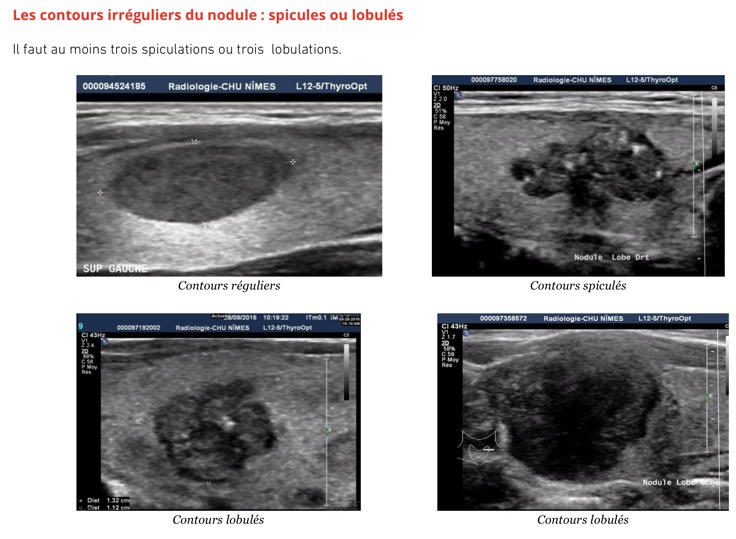

Se méfier des formations hypoéchogènes